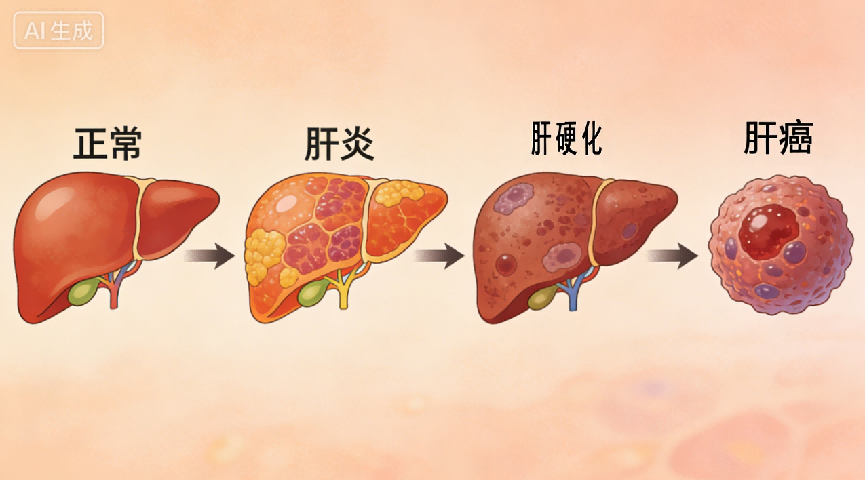

在我国,乙型肝炎尤为突出。根据国家卫健委2019年数据,我国乙肝病毒感染者约7000万,其中慢性乙型肝炎患者约2000万至3000万。乙型肝炎之所以令人担忧,是因为其中约三分之一可能发展为慢性肝炎,而这些慢性患者中又约有三分之一可能进一步进展为肝硬化甚至肝癌。

疾病可表现为乏力、恶心、食欲不振、厌油、腹胀、尿黄、肝区不适等症状,严重者可出现肝掌、蜘蛛痣,甚至意识改变、嗜睡等神经系统症状。若未能有效控制,病情可逐渐进展为肝硬化或肝癌。

由于肝脏代偿能力较强,早期常无明显症状,发现时往往已进入中晚期。传统药物治疗存在一定局限性,因为多数药物需经肝脏代谢,不恰当的用药反而可能加重负担。对于终末期肝病,肝移植是目前有效手段,但面临供体短缺、免疫排斥等问题。